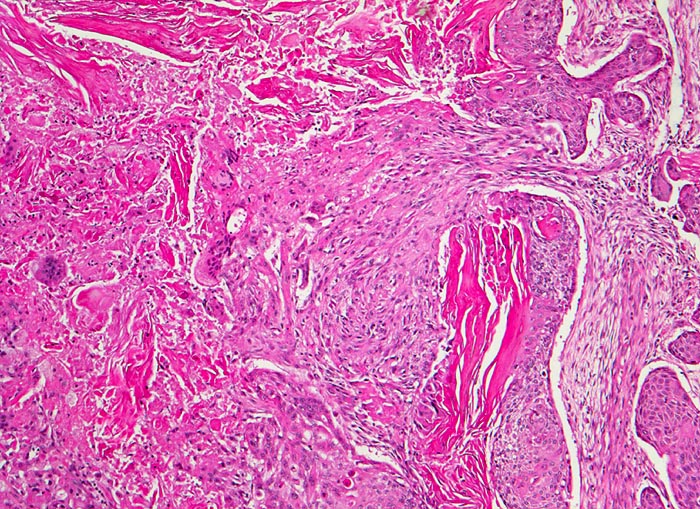

PathoPic – image database / PathoPic ID 4725 - verhornendes Plattenepithelkarzinom

verhornendes Plattenepithelkarzinom

Lunge

Das Tumorgewebe bildet solide Zellstränge, welche eingebettet sind in ein lockeres desmoplastisches Stroma. Im Zentrum der Zellstränge grosse Mengen von Hornlamellen, welche teilweise nekrotisch zerfallen.

Zentrales Bronchuskarzinom des rechten Lungenoberlappens von 5cm Durchmesser. Lungenoberlappenresektion.

100